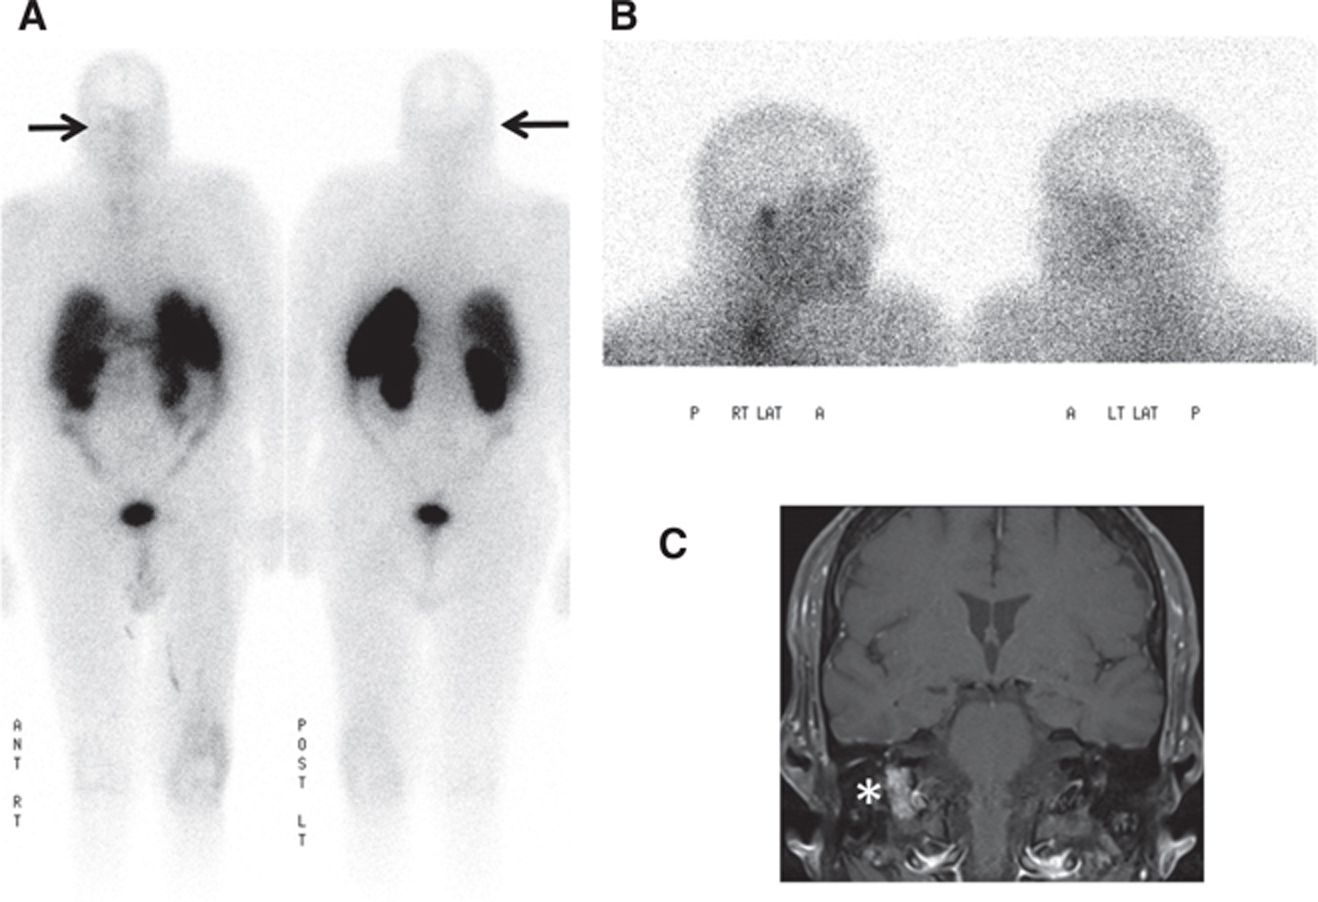

SPECT/CT improves sensitivity and specificity (Figure 6); in one case series, MIBG SPECT/CT was shown to increase diagnostic certainty in 89% of discordant CT and planar MIBG cases (41, 42).

Fig 6

Figure 6 A 40-year-old male patient with elevated catecholamines. (A) Whole body planar images, (B) coronal and axial attenuation-corrected SPECT images, and (C) axial non-enhanced CT and fused SPECT/CT images of the right adrenal region demonstrate a 4 cm × 3 cm × 4 cm soft tissue lesion with intense I-123 MIBG uptake much greater than hepatic uptake consistent with a biopsy-proven pheochromocytoma.

Fig 7

Figure 7 A 65-year-old male patient with right middle ear cavity mass. (A) In-111 pentetreotide whole body planar and (B) lateral spot images of the head performed 24 h after administration of radiotracer show moderate focal tracer uptake in the region of the right middle ear. (C) T1-weighted fat-suppressed post-contrast coronal brain MRI shows an avidly enhancing mass in the right jugular foramen concerning for a glomus tumor. Surgical pathology showed a 1.2 cm × 0.6 cm × 0.3 cm lesion with positivity for synaptophysin and chromogranin on immunohistochemistry, compatible with a paraganglioma.